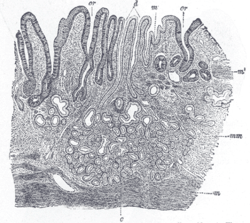

Like the other parts of the gastrointestinal tract, the stomach walls consist of an outer mucosa, and inner submucosa, muscularis externa, and serosa.

The gastric mucosa of the stomach consists of the epithelium and the lamina propria (composed of loose connective tissue), with a thin layer of smooth muscle called the muscularis mucosae separating it from the submucosa beneath. The submucosa lies under the mucosa and consists of fibrous connective tissue, separating the mucosa from the next layer. Meissner's plexus is in this layer. The muscularis externa lies beneath the submucosa, and is unique from other organs of the gastrointestinal tract, consisting of three layers:

- The inner oblique layer: This layer is responsible for creating the motion that churns and physically breaks down the food. It is the only layer of the three which is not seen in other parts of the digestive system. The antrum has thicker skin cells in its walls and performs more forceful contractions than the fundus.

- The middle circular layer: At this layer, the pylorus is surrounded by a thick circular muscular wall which is normally tonically constricted forming a functional (if not anatomically discrete) pyloric sphincter, which controls the movement of chyme into the duodenum. This layer is concentric to the longitudinal axis of the stomach.

- Auerbach's plexus (AKA myenteric plexus) is found between the outer longitundinal and the middle circular layer and is responsible for the innervation of both (causing peristalsis and mixing)

- The outer longitudinal layer

The stomach also possesses a serosa, consisting of layers of connective tissue continuous with the peritoneum.

The gastrointestinal wall of the stomach.